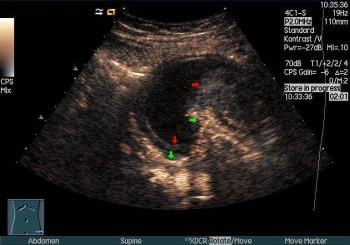

CEUS permite vizualizarea structurilor vasculare și parenchimatoase în timp real (lafel ca și CT sau IRM), în paralel cu imaginea ecografică standard. Este o investigație neinvazivă, cu riscuri minime, care oferă informații valoroase ca și alte tehnici imagistice de vârf (CT, IRM, PET).

Principiul ecografiei cu substanță de contrast constă în proprietatea microbulelor de a-și modifica dimensiunea ca răspuns la stimularea cu ultrasunete. Oscilația volumului lor generează ecouri de frecvențe diferite către sonda de ecograf și conferă astfel contrastul spațiului vascular cu parenchimul adiacent. Există 2 fenomene principale în ecografia cu substanță de contrast: amplificare (enhancement) și spălare (washout), pe baza cărora se stabilește caracterul leziunii cercetate. Este foarte important ca ecograful să fie bine calibrat înaintea începerii unei examinări și în special ca MI (mechanical index) să fie scăzut (sub valoarea normală folosită în ecografia standard) pentru că altfel bulele vor fi distruse. Chiar dacă se pierde puțin din rezoluție ca urmare a modificării frecvenței ultrasunetelor (imaginea este puțin mai zgomotoasă comparativ cu cea a ecografiei standard în mod B), contrastul parenchim-vase de sânge este foarte bun; în cazul în care imaginea ecografică standard (mod B) este suboptimă, imaginea CEUS va fi probabil dezamăgitoare.

Înainte de realizarea ecografiei cu substanță de contrast se efectuează o ecografie standard (mod B și mod Doppler). Se cateterizează o venă periferică (preferabil vena antecubitală) cu un ac de diametru mai mare decât cel uzual (20-22 Gauge) și se pregătește substanța de contrast în dispozitivul din kitul oferit de firma producătoare. Se injectează în bolus substanța de contrast, după care se împinge coloana de bule prin injectarea pe aceeași linie venoasă a 5-10 ml ser fiziologic. Ecografistul trebuie să fie cu transductorul pe leziune și să înceapă înregistrarea imaginii imediat după injectarea substanței de contrast, deoarece prima fază (cea arterială) apare rapid (în 10-20 secunde). În momentul injectării microbulelor, pacientul nu simte nimic. În fapt, procedura este complet nedureroasă, dacă nu luăm în considerare venopuncția. Examinatorul va urmări pe ecranul ecografului și va înregistra imaginile cu timpii vasculari care corespunând pătrunderii agentului de contrast în microvascularizație: pentru parenchimul hepatic – faza arterială (începe la 10-20 sec și se termină la 25-35 sec), faza portală-venoasă (începe la 30-45 sec și se termină la 120 sec) și faza tardivă (după 120 sec până la 240-360 sec). La finalul examinării, examinatorul distruge microbulele prin creșterea MI (mechanical index) la valoarea normală folosită în ecografiile diagnostice standard (pentru ecografia cu substanță de contrast se recomandă un MI de 0.05-0.25, optim sub 0.10). Există și posibilitatea administrării continue de substanță de contrast, prin perfuzie intravenoasă.